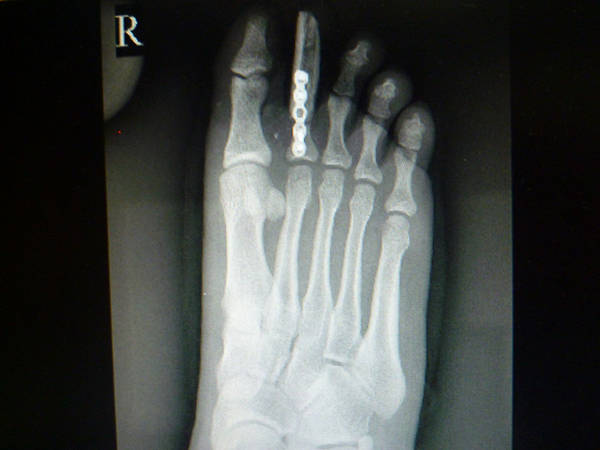

[手指再造] 拇再造术后供区的另一种修复(12.23随访照片来了)

1.jpg 2.jpg 3.jpg 4.jpg 5.jpg 6.jpg 7.jpg 8.jpg 9.jpg 10.jpg 11.jpg 12.jpg 13.jpg

功能和外观都很好,学习了,池主任的病人应该感到幸运和幸福